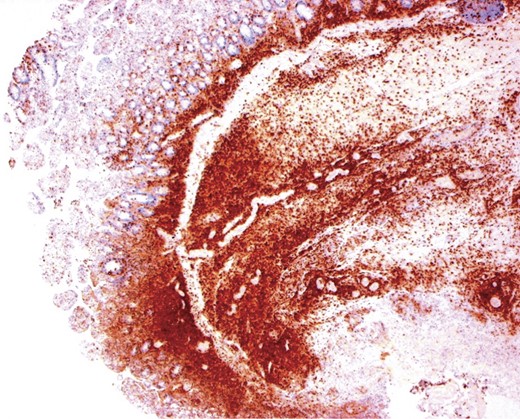

Immunohistochemical staining confirmed the lymphocytes adjacent to the areas of ulceration were CD3+ T cells, co-expressing CD8 but negative for CD4 and CD5 (Fig. 3). The immunoprofile of lymphocytes seen in association with coeliac disease amounted to an EATCL.

CD8 immunohistochemical stain, small bowel: brown staining indicating the CD8+ T lymphocytes in the mucosa and remaining bowel wall. The large amount of T-lymphocytes is surprising given the more subtle H&E appearance.